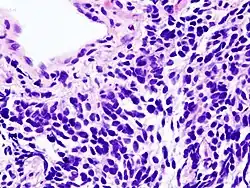

| Micrograph of a small-cell carcinoma of the lung showing cells with nuclear moulding, minimal amount of cytoplasm and stippled chromatin. FNA specimen. Field stain. | |

Small-cell carcinoma is an undifferentiated neoplasm composed of primitive-appearing cells. As the name implies, the cells in small-cell carcinomas are smaller than normal cells and barely have room for any cytoplasm. Some researchers identify this as a failure in the mechanism that controls the size of the cells.[32]